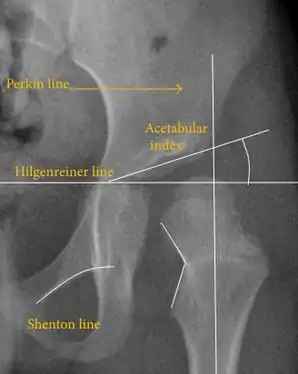

Незважаючи на широке поширення ультразвуку, рентген малого тазу все ще часто використовується для діагностики або моніторингу дисплазії кульшового суглоба або для оцінки інших вроджених станів або пухлин кісток[43]. Найбільш корисні лінії та кути, які можна провести в дитячому тазі для оцінки дисплазії кульшового суглоба, такі: (У дорослих застосовують інші виміри!)